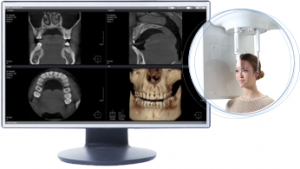

L’esame ha la durata di pochi secondi e può essere eseguito sia in piedi che in posizione seduta.

Il tomografo cone beam è esteticamente simile ad un ortopantomografo ed il posizionamento del paziente è semplice, del tutto simile a quello di un comune esame di ortopantomografia delle arcate dentarie con durata dell’esame superiore di solo qualche secondo.